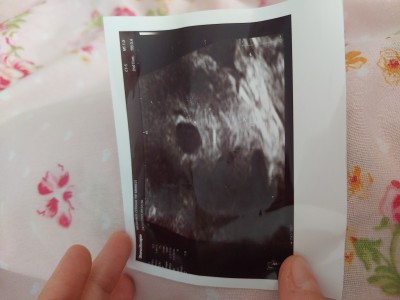

Kizlar 28 ekimde transfer oldum 8 kasimda sonucumu aldim.ve pozitif fakat şöyle bir karmaşıklık var kendi doktoruma göre 6+2 günlüğüm fakat baska bir doktora göre de 5 hafta içerisindeyim 17 kasimda kese gördük 24 kasimda kalp atışı duyarız dedi kendi doktorum kalp atışı yoktu ve yolk kesesi embriyo da yok dedi ve haftaya bakicaz ama iyi bisey degil dedi  ben baska doktora da gittim o doktor 5 hafta icinde olduğumu ve bu zamanlarda gozukmemesi normal dedi  bu dünkü kendi doktorumun yaptığı usg resmi büyük yuvarlak olan  diğeri de bu baska doktorun çektiği de bu